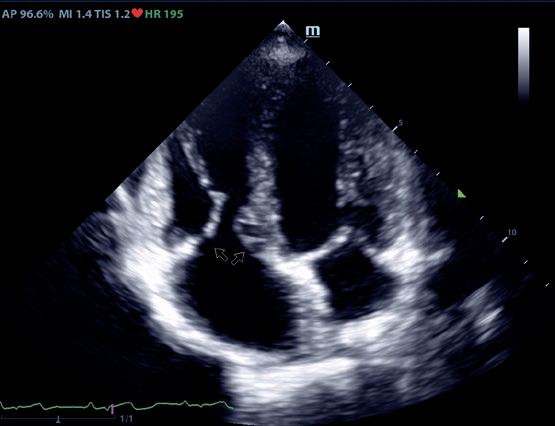

Al mencionar las aplicaciones más frecuentes de la ecocardiografía en el campo de la anestesiología, Xavi Navarro se centró en la evaluación preanestésica, así como en la de la volemia y la respuesta a fluidos.

Ecografía aplicada a la evaluación cardiaca y hemodinámica en anestesia

Xavi Navarro también remarcó el trabajo multidisciplinar, destacando la labor realizada conjuntamente por cardiólogos y anestesiólogos, y comentó que la ecografía permite realizar una evaluación rápida, a tiempo real y no invasiva de la estructura y función cardiacas, de manera que se pueden optimizar la seguridad y el manejo cardiovascular del paciente.

Al mencionar sus aplicaciones más frecuentes en el campo de la anestesiología, se centró en la evaluación preanestésica y en la de la volemia y la respuesta a fluidos, aunque también hizo referencia a la monitorización hemodinámica durante la anestesia y durante la recuperación, así como a la detección de complicaciones intra y posoperatorias:

• Con respecto a la evaluación preanestésica, recomendó realizarla a animales de razas predispuestas a las cardiopatías, así como a los sénior o a los que tengan signos clínicos que sugieran enfermedad avanzada. No obstante, puesto que “hay que tener cuidado con los pacientes asintomáticos y con los gatos”, en general recomendó realizar un estudio ecocardiográfico siempre que sea posible.